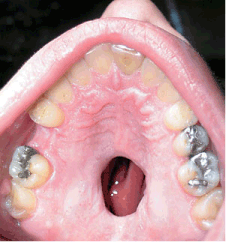

El caso, con la imagen de la derecha, aparece esta semana en la revista médica 'The New England Journal of Medicine'. "El paciente tenía un consumo muy abusivo de cocaína y sabía que esta era la causa de su problema", cuenta Lypka a elmundo.es. De hecho, cuando Lypka y su colega Mark Urata, ambos del departamento de medicina de la Universidad del Sur de California (EEUU), examinaron al paciente: "fue comunicativo sobre su historial de abuso. La historia y el examen clínico encajaban, lo que resolvió el diagnóstico: perforación palatal inducida por cocaína", relata el cirujano.

Lesión del paciente estadounidense. (Foto: 'The New England Journal of Medicine' ©2007)